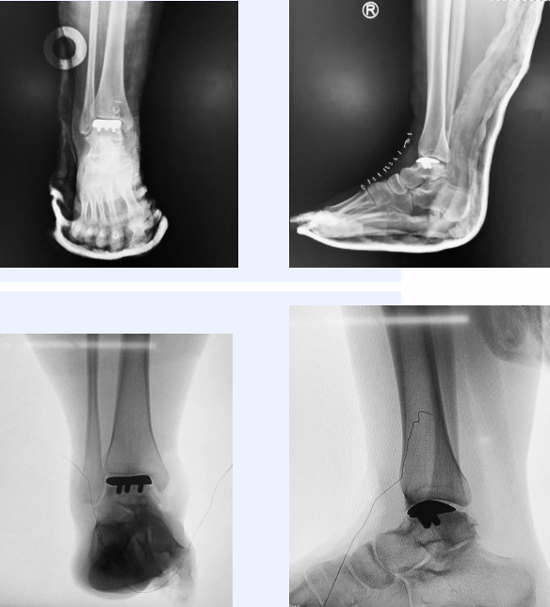

术后透视照

在3D打印导板的辅助下,截骨精准顺利,定制化的假体植入后,女孩的踝关节恢复了正常的活动度,且最大量的保留了正常骨量,她和家人悬着的心终于放下了。“是武主任团队带我迈进了大学校园的第一步。”希望女孩在未来的大学生活里,脚踏实地,努力奔跑,早日实现自己的人生理想。